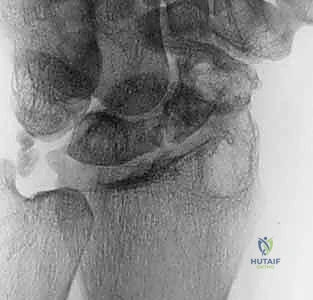

يتم فتح كبسولة مفصل الرسغ للوصول إلى العظم الزورقي المكسور. يقوم الدكتور هطيف بتنظيف منطقة عدم الالتحام بالكامل، وإزالة كل الأنسجة الليفية، والتكيسات، والعظام الميتة (النخرية) باستخدام أدوات دقيقة (Curettes) ومثاقب صغيرة، حتى يصل إلى حواف عظمية صحية تنزف دماً (علامة على الحيوية). هذا يترك فجوة بحاجة إلى الحشو.

![تحضير وتجهيز العظم الزورقي لاستقبال الطعم](/media/hutaif_opertive/hutaif-ch